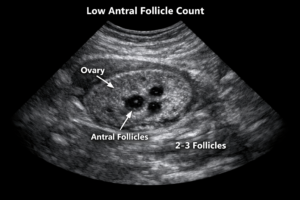

After three failed IVF attempts elsewhere, we were losing hope. Dr Ankush Raut's expertise in handling complex cases like my poor ovarian reserve gave us new hope. His personalized treatment approach and innovative protocols made all the difference. His compassionate nature helped us stay positive throughout the journey. Today, we're blessed with twins, all thanks to Dr Raut's excellence at Apollo Fertility.